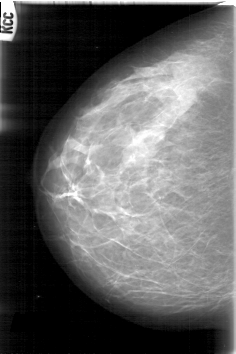

D_4006_1.RIGHT_CC

RIGHT_CC LINES 5296 PIXELS_PER_LINE 3526 BITS_PER_PIXEL 12 RESOLUTION 43.5 NON_OVERLAY